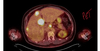

Describe the epidemiology of Colorectal cancer

What’s the histopathology of colorectal cancer

Adenocarcinoma

Describe the pathogenesis of colorectal cancer